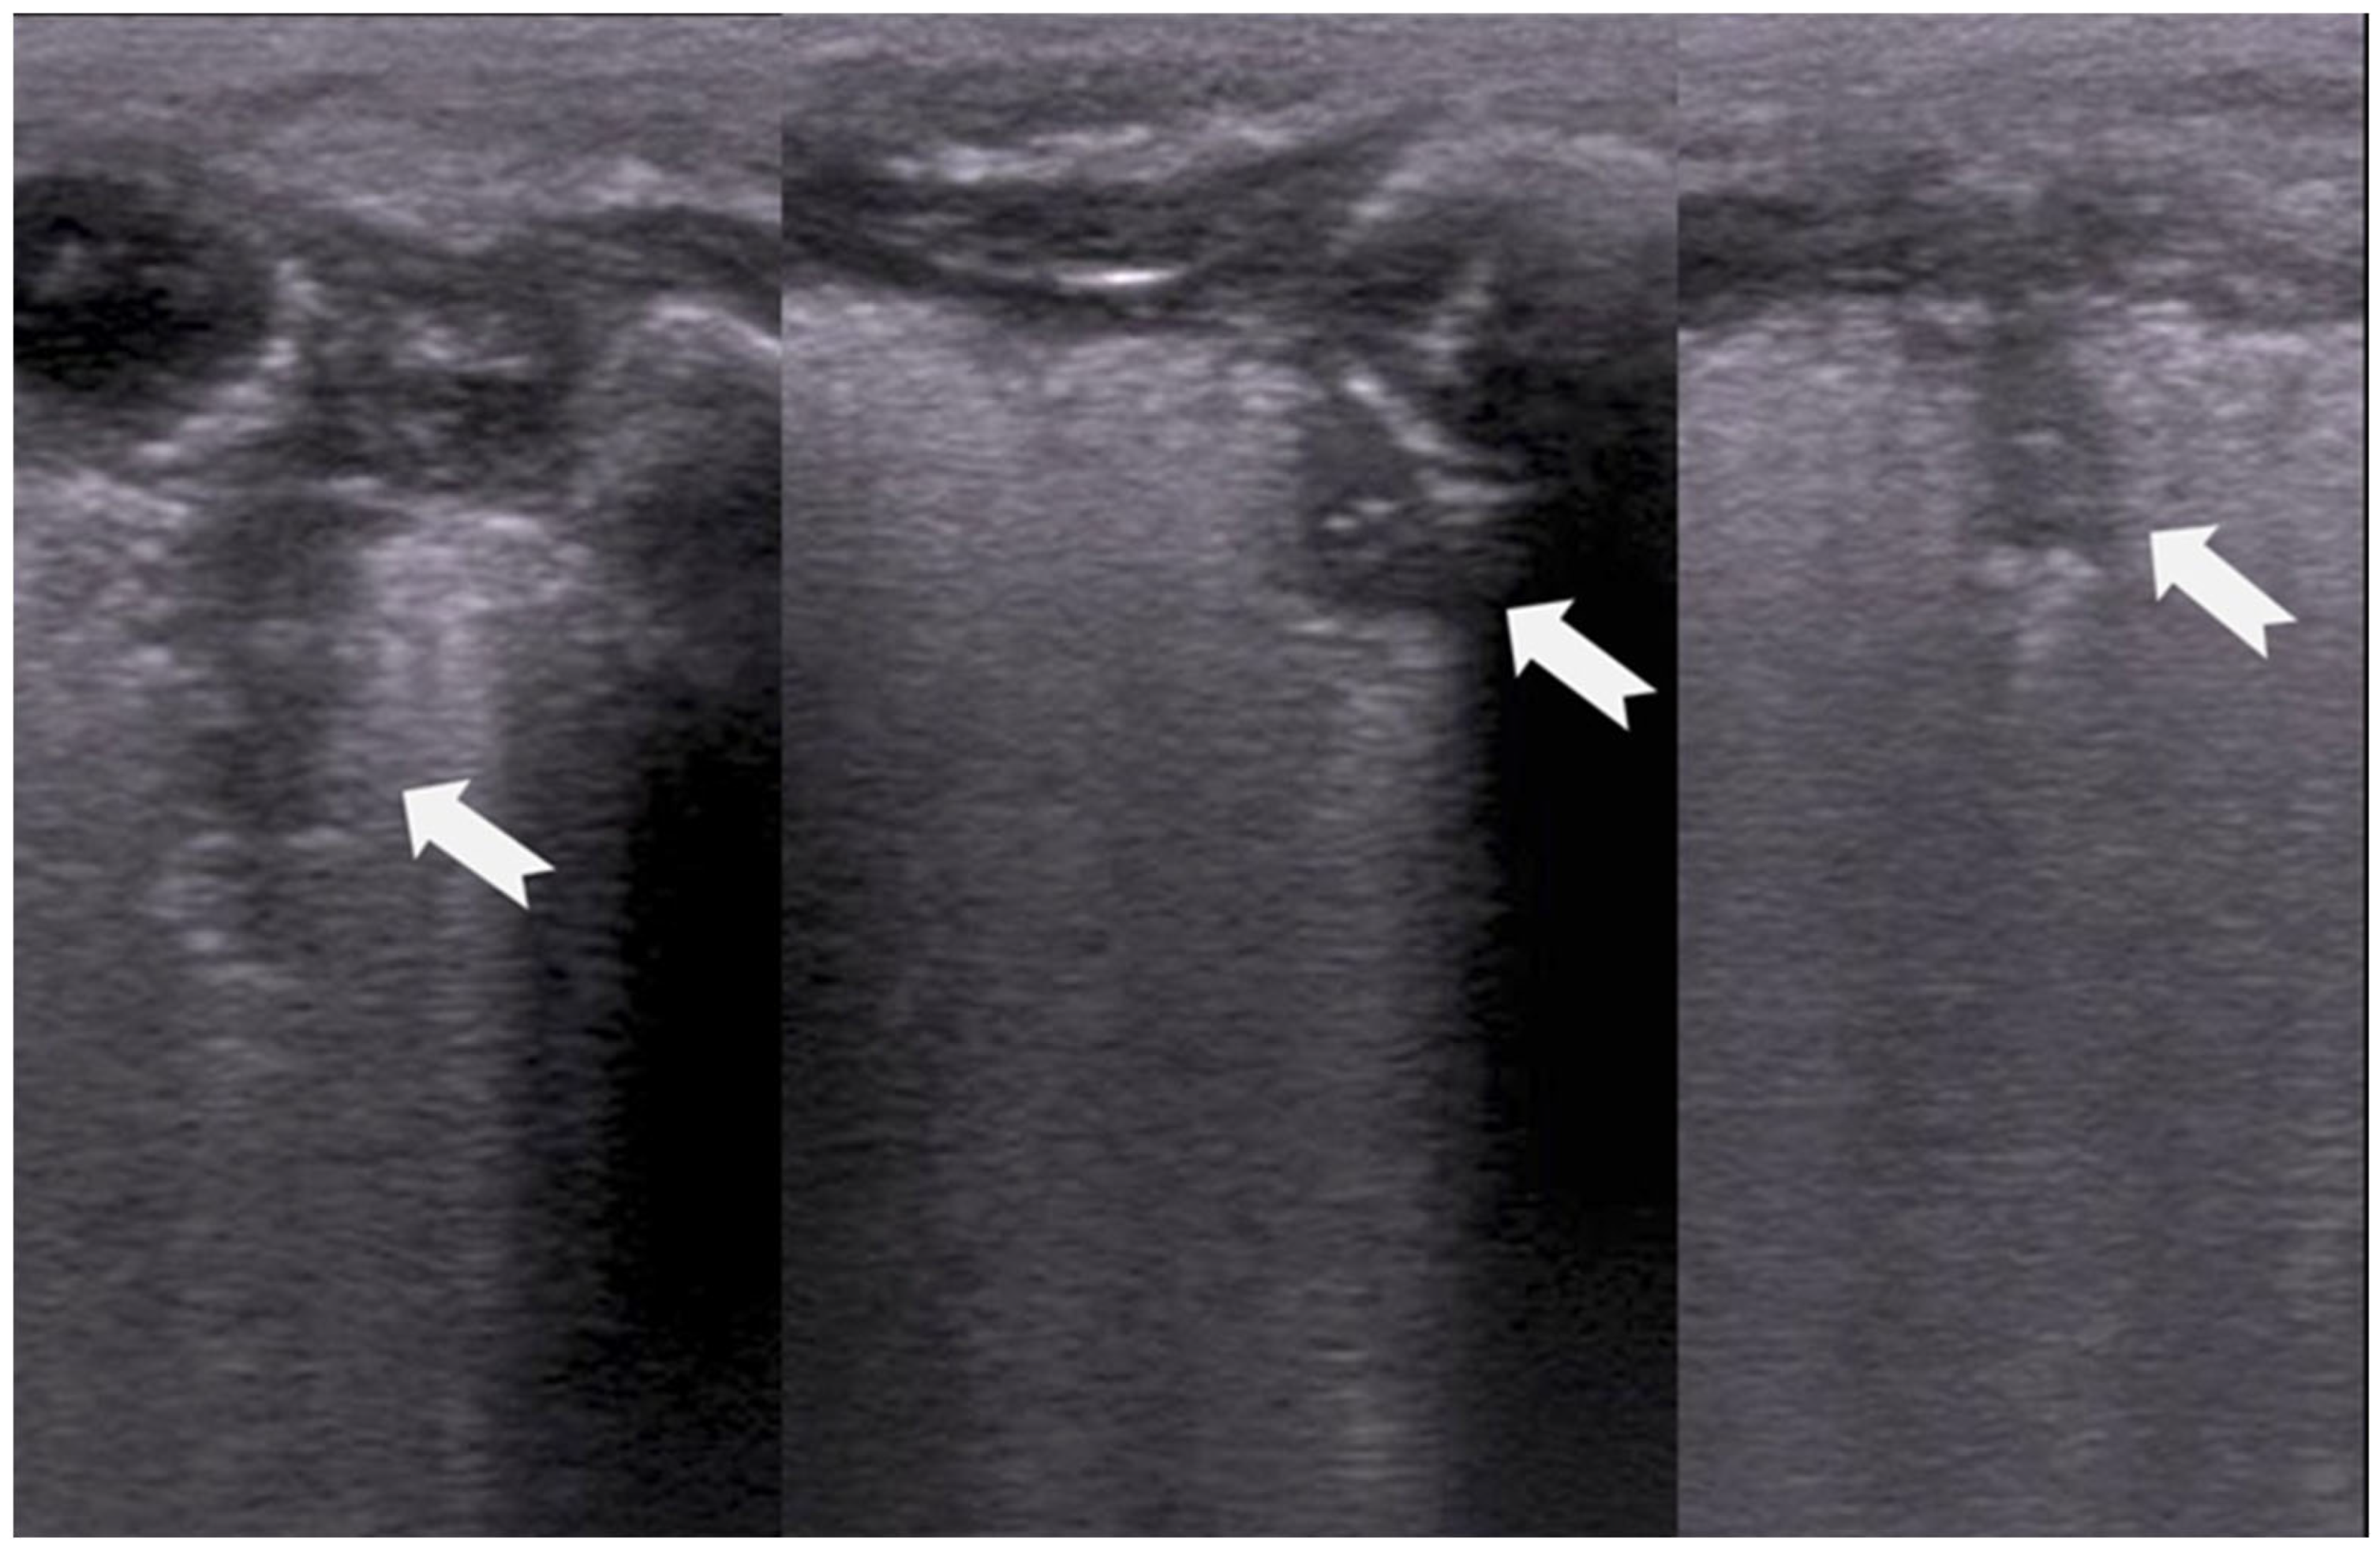

RDS is a common cause of neonatal respiratory failure, particularly in preterm infants, resulting from surfactant deficiency and alveolar collapse. LUS has become a valuable diagnostic tool for RDS, offering real-time visualization of lung pathology at the bedside [38,42,43,44,45]. A hallmark sonographic feature of RDS is the presence of dense, confluent B-lines throughout the lung fields, producing a “white lung” appearance due to the loss of normal aeration. Notably, the whole lung is typically involved, with a diffuse, bilateral distribution that distinguishes RDS from more localized pulmonary conditions [37,46,47]. Additionally, interspersed consolidations may be present, including hypoechoic and subpleural areas of alveolar collapse, reflecting regions of complete de-aeration. These consolidations often lack air bronchograms and are associated with irregular or thickened pleural lines. The combination of diffuse B-line patterns, global lung involvement, and patchy consolidations provides a highly suggestive ultrasound profile of RDS and facilitates early diagnosis. In addition, for RDS, LUS may be used for severity assessment and the monitoring of treatment response in the neonatal intensive care setting [16,20,27,29]. The ability of the LUS to characterize the severity of the RDS is debatable (Figure 14 and Figure 16) [48].

Figure 15.

Severe RDS with sub-segmental(-pleural) consolidations. by LUS.